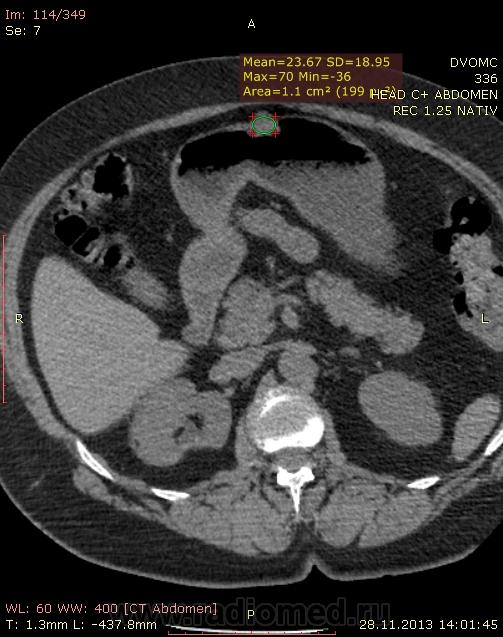

Пациентка 66 лет. В 2010 году мастэктомия слева - Cr II B ст., псориаз. Я нашел: образование нижнего полюса правой почки, образование в антральном отделе желудка по малой кривизне, киста яичника слева...в желчном пузыре много газосодержащих камней(?), лимфоузлов вроде не видно. Всё, кроме образования желудка находили ранее на УЗИ да на МРТ. Коллеги, посмотрите, можт я чё пропустил или неправильно понял. Какие мысли по поводу образований - особенно желудка(GIST? mts?)  DICOM здесь http://files.mail.ru/2C4F7CA79A884D37B3C86FF69C3D8D67

Мне кажется, что маловато контраста на вес пациентки. Почечно-клеточная (как более вероятная) карцинома правой почки, в стенке желудка написала бы мтс. Газосодержащие камни желчного пузыря. Кистовидное образование яичника. Киста печени, кисты почек. Дивертикулез толстой кишки. А что с жиром в грыже (вроде пупочная))) - наверное, последствие инфаркта сальника.